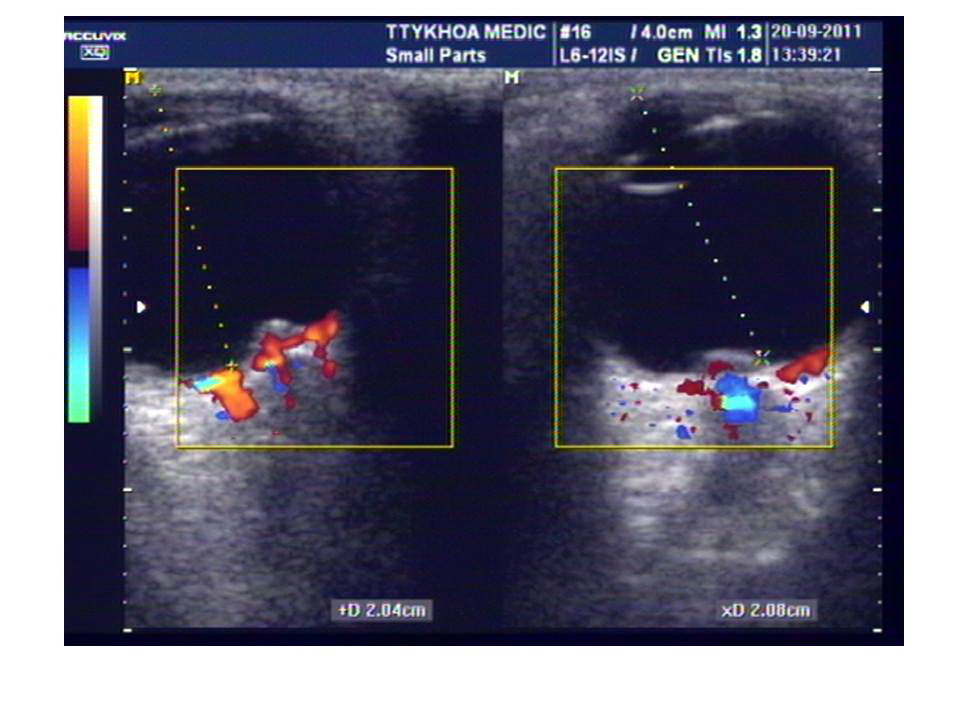

Siêu âm mắt xác nhận có phù gai thị 2 bên, đường kinh bao dây thần kinh thị giác bên P=5,1mm, bên T=5,5mm.

Siêu âm mắt nghĩ đến tăng áp lực nội sọ, đề xuất chụp MDCT não tìm nguyên nhân tăng áp nội sọ. Trên phim MDCT, thấy 1 u từ đám rối màng mạch não thất bên, có vôi hóa, khoảng 30mm, gần lỗ Monro và giãn não thất bên bên T nhiều hơn bên P.